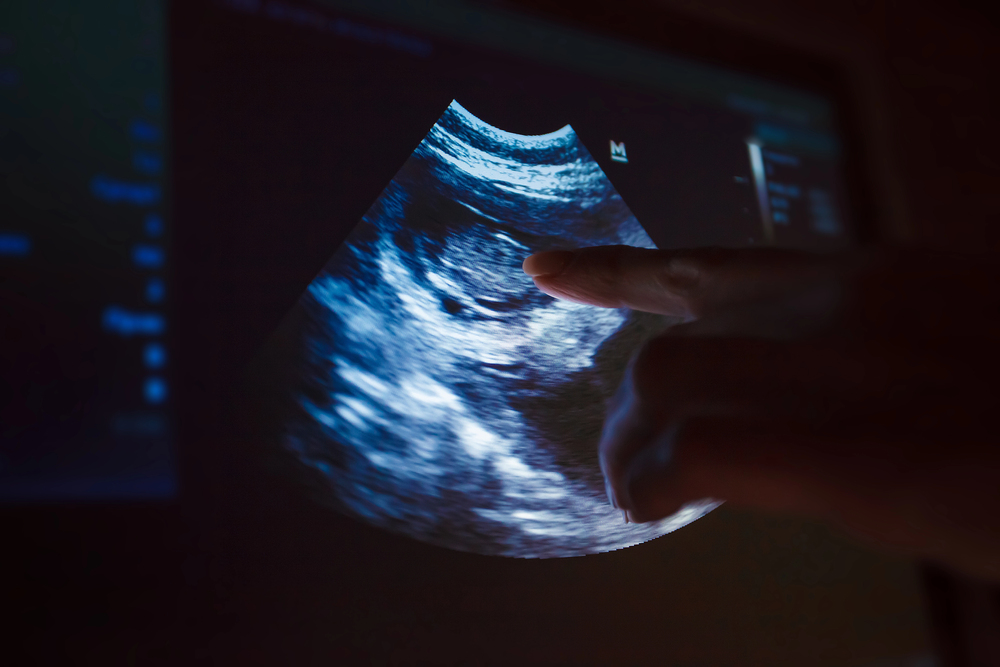

Ecografías

Contamos con ecógrafo portátil para ofrecerte diagnósticos precisos allí donde estés. Evaluamos tejidos blandos, lesiones musculares, tendones, ligamentos, reproducción y otros aspectos clave. La imagen nos permite actuar a tiempo y ajustar los tratamientos con mayor seguridad.